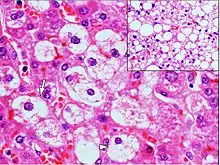

Micrograph demonstrating marked (macrovesicular) steatosis in non-alcoholic fatty liver disease. Masson's trichrome stain.

Steatosis reflects an impairment of the normal processes of synthesis and elimination of triglyceride fat. Excess lipid accumulates in vesicles that displace the cytoplasm. When the vesicles are large enough to distort the nucleus, the condition is known as macrovesicular steatosis; otherwise, the condition is known as microvesicular steatosis. While not particularly detrimental to the cell in mild cases, large accumulations can disrupt cell constituents, and in severe cases the cell may even burst.

Histopathology of microvesicular steatosis, with foamy hepatocytes (two annotated by arrows), as opposed to macrovesicular steatosis (insert).

Microvesicular steatosis is characterized by small intracytoplasmic fat vacuoles (liposomes) which accumulate within hepatocytes.[9] Common causes are tetracyclines, acute fatty liver of pregnancy, Reye's syndrome, and hepatitis C.

Histology

Histologically, steatosis is physically apparent as lipid within membrane bound liposomes of parenchymal cells.[2] When this tissue is fixed and stained to be better viewed under a microscope, the lipid is usually dissolved by the solvents used to prepare the sample. As such, samples prepared this way will appear to have empty holes (or vacuoles) within the cells where the lipid has been cleared. Special lipid stains, such as Sudan stains and osmium tetroxide are able to retain and show up lipid droplets, hence more conclusively indicating the presence of lipids. Other intracellular accumulations, such as water or glycogen, can also appear as clear vacuoles, therefore it becomes necessary to use stains to better determine what substance is accumulating.